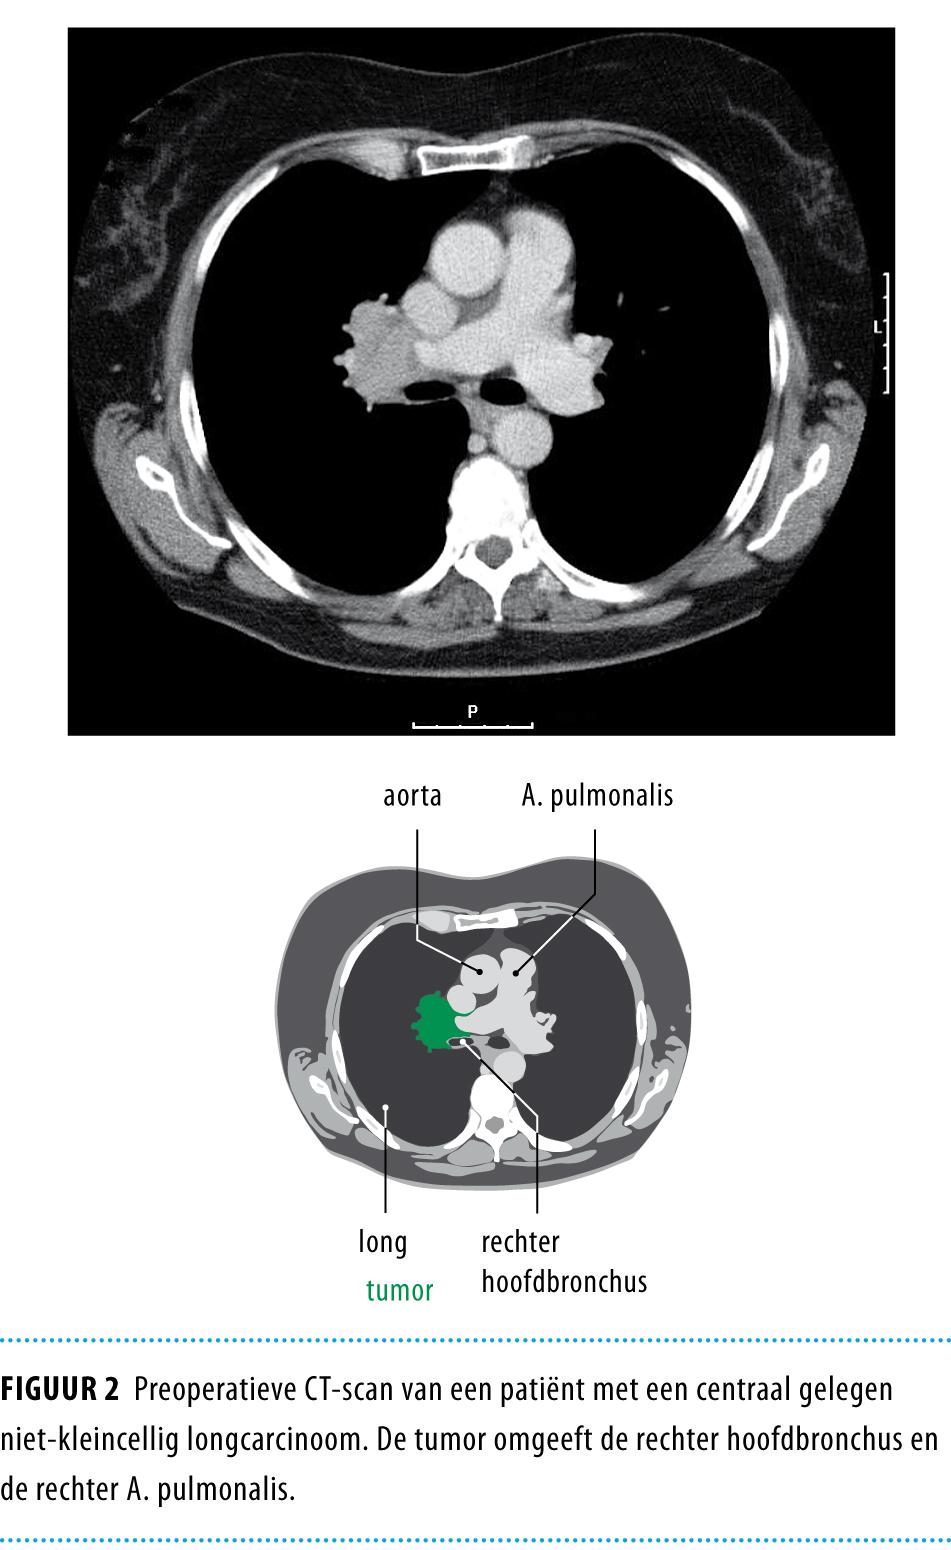

Voor elke patiënt werd in een wekelijks multidisciplinair overleg het diagnostisch traject en de behandelstrategie bepaald. In dit overleg participeerden longartsen, cardio-thoracaal chirurgen, pathologen, radiotherapeuten, radiologen en nucleair geneeskundigen. Bij het overwegen van een parenchymsparende operatie speelt de ingeschatte resectabiliteit van de tumor op basis van beeldvormend onderzoek een rol (figuur 2), met dien verstande dat slechts zelden op basis van beeldvormend onderzoek alleen kan worden besloten dat een tumor zeker irresectabel is. Tevoren moet bekend te zijn of een eventuele pneumonectomie haalbaar is op basis van de geschatte resterende longfunctie.

Figuur 2